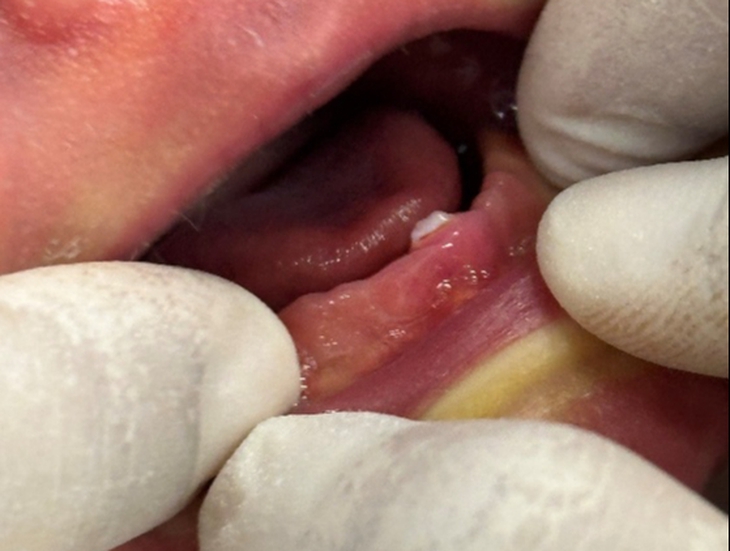

Ban đầu, viêm lợi thường chỉ biểu hiện qua các dấu hiệu như sưng đỏ và chảy máu khi đánh răng. Tuy nhiên, theo thời gian, vi khuẩn có thể xâm nhập sâu hơn vào các mô nâng đỡ răng, gây phá hủy xương ổ răng và dẫn đến viêm nha chu. Thống kê từ CDC (Mỹ) vào năm 2009 và năm 2010 cho thấy gần 50% người trưởng thành trên 30 tuổi mắc viêm nha chu, đáng lo ngại là nhiều người trong số đó không hề nhận thức được tình trạng này.